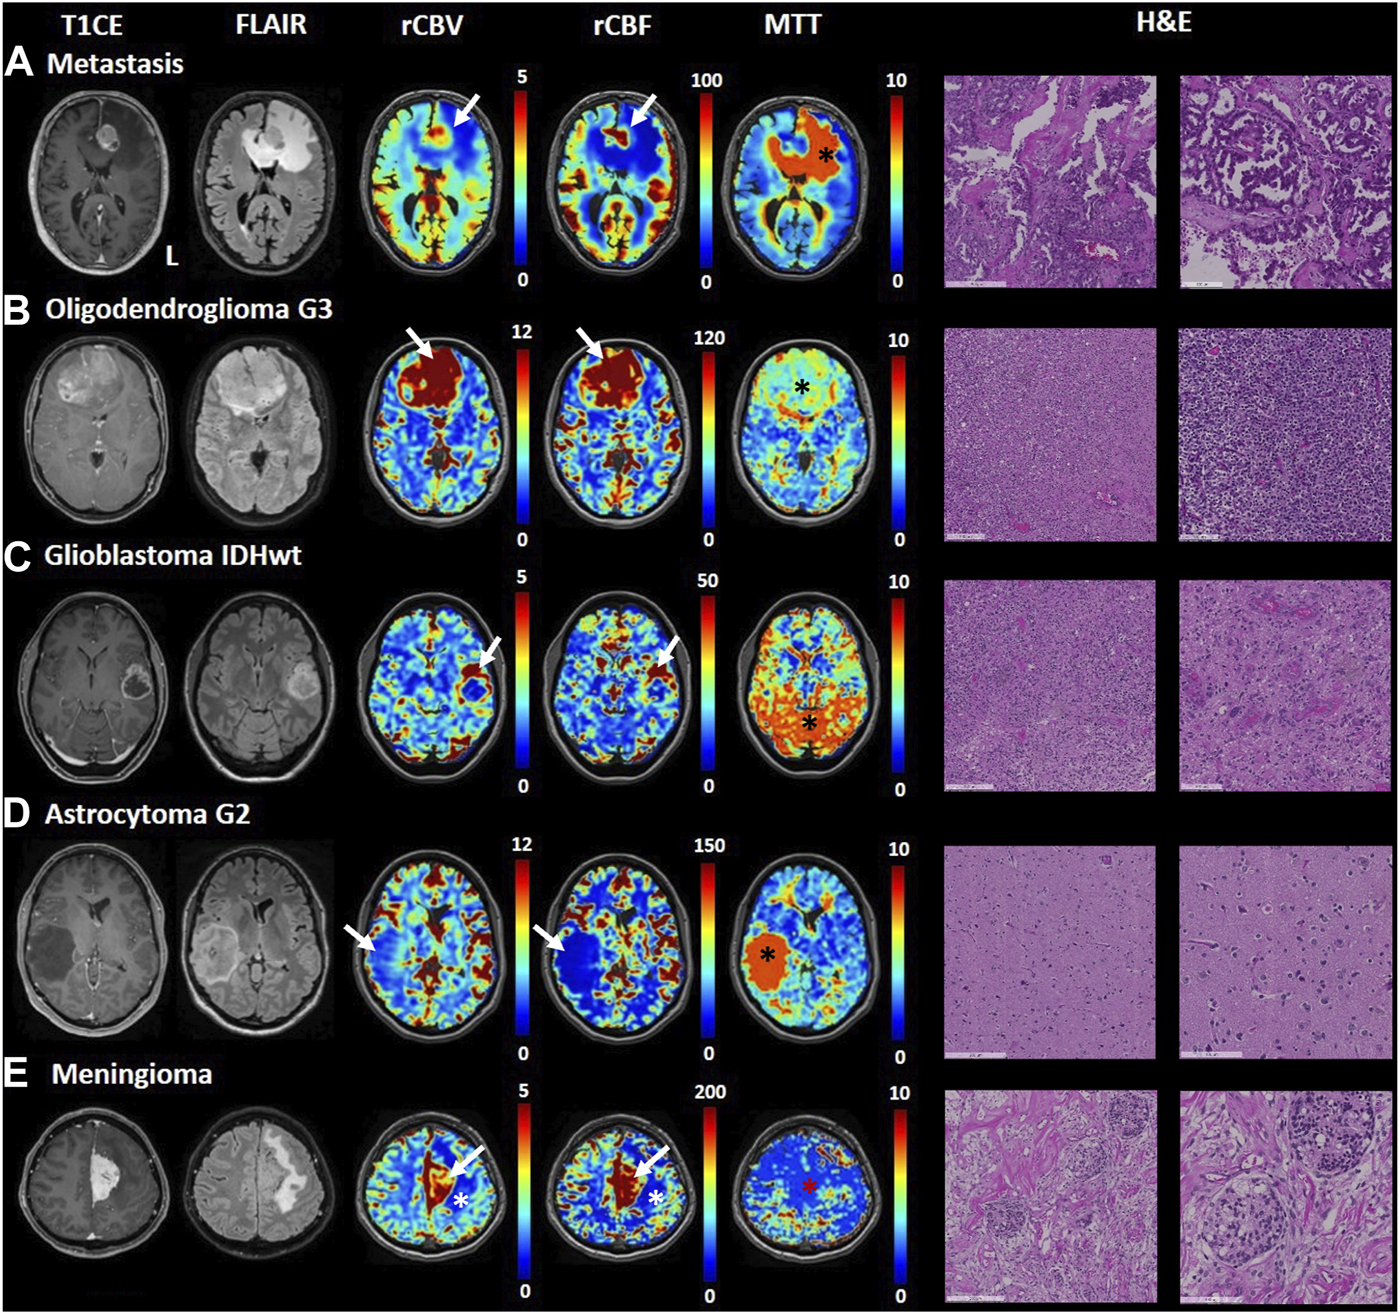

Figure 2 shows an illustrative case, i.e., patient 2, 58 y. o. male with a left frontobasal glioblastoma. The perfusion maps show high CBV, CBF in the contrast-enhanced lesion regions, while these metrics are very low in the central necrotic area with high agreement with the morphological high-resolution sequences. MTT is mostly increased in peritumoral edematous tissue. Figure 3 displays perfusion patterns in different tumor types. Qualitative image analysis shows perfusion to be higher in grey matter than in white matter and increased CBV and CBF were observed in contrast-enhancing lesion of metastases (Figure 3A), oligodendroglioma WHO grade 3 (Figure 3B), glioblastoma (Figure 3C) and meningioma (Figure 3E) with respect to healthy tissue. On the contrary, lower CBV and CBF were observed in the astrocytoma WHO grade 2 (Figure 3D). MTT was shown to be higher in areas of edema identified by T2 FLAIR (Figures 3A, B) as well as in the astrocytoma WHO grade 2 dense cellular tissue (Figure 3D).

FIGURE 3

Transient hypoxia induced-dOHb MRI perfusion patterns in some common brain tumors. T1-CE, T2-FLAIR, rCBV, rCBF and MTT transient hypoxia induced-dOHb MRI perfusion maps and H&E sections are displayed for each tumor type included. (A). Patient with a left frontal lung adenocarcinoma metastasis. Around the contrast-enhancing lesion, displaying high CBV and CBF (white arrow) can be appreciated an extensive perilesional edema (FLAIR hyperintensity, low CBV and CBF, high MTT - black asterisk). (B). Patient with frontobasal oligodendroglioma grade 3, displaying strongly increased CBV and CBF (white arrows) as well as moderately increased MTT (black asterisk). (C). Patient with left superior temporal gyrus glioblastoma. The contrast-enhancing lesion (high CBV and CBF, white arrows) surrounding a central necrotic area can be appreciated. The MTT map shows spot-like increased values, particularly evident in the posterior circulation (black asterisk) which we speculate could be attributed to noisier signal/suboptimal stimulus, (D). Patient with right middle temporal gyrus astrocytoma grade 2. The lesion does not show contrast uptake, is hyperintense in FLAIR sequence and displays lower perfusion than healthy parenchyma (low CBV and CBF shown by white arrow) as well as strongly increased mean transit time (black asterisk). (E). Patient with a left-sided falx meningioma. FLAIR sequence shows hyperintense edema around the contrast-enhancing lesion (note increased CBV and CBF as pointed by white arrows). The MTT map shows no increased mean transit time in the lesion (red asterisk).